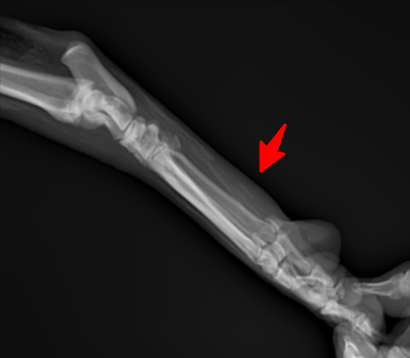

다친발 사진

우선 엑스레이 사진상 명확한 비정상적 구조가 보입니다.

화살표로 표시된 부분의 근육 혹은 인대의 석회화 양상이 매우 뚜렷한 양상을 보이고 있고, 이는 양측 후지 모두에서 관찰되는 바 대사성 질환이나 전신성 질환이 있을 가능성이 높고,

화살표 한 부분이 반대쪽에 비해 부종 양상이 명확하게 관찰되기 때문에 근육 및 인대의 석회화를 유발하는 질환 https://diamed.tistory.com/1023 이 원발로 있다가 충격에 의해 인대나 근육이 찢어졌을 가능성이 높다는것을 의미합니다.